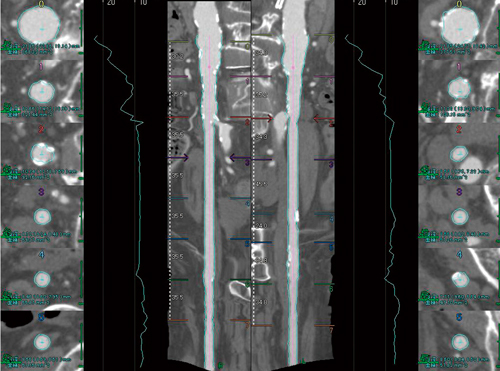

大動脈ステントグラフト内挿術では,アクセスする血管の選択も重要である。胸部ステントグラフトでは,最大で26F(8.6mm)程度の内腔がアクセスに必要な場合があり,より内腔が広く,石灰化の少ないアクセスを選択する必要がある。ソフトウェア上では,1画面に2つの血管軸のストレートCPR画像および内径の変化グラフを横に並べて比較することができ,アクセス血管の評価,決定にしばしば用いられる(図4)。

図4 二枝比較画面

左右の腸骨動脈のストレートCPRとトレンドグラフを並べ,アクセスの血管の性状が容易に比較評価できる。